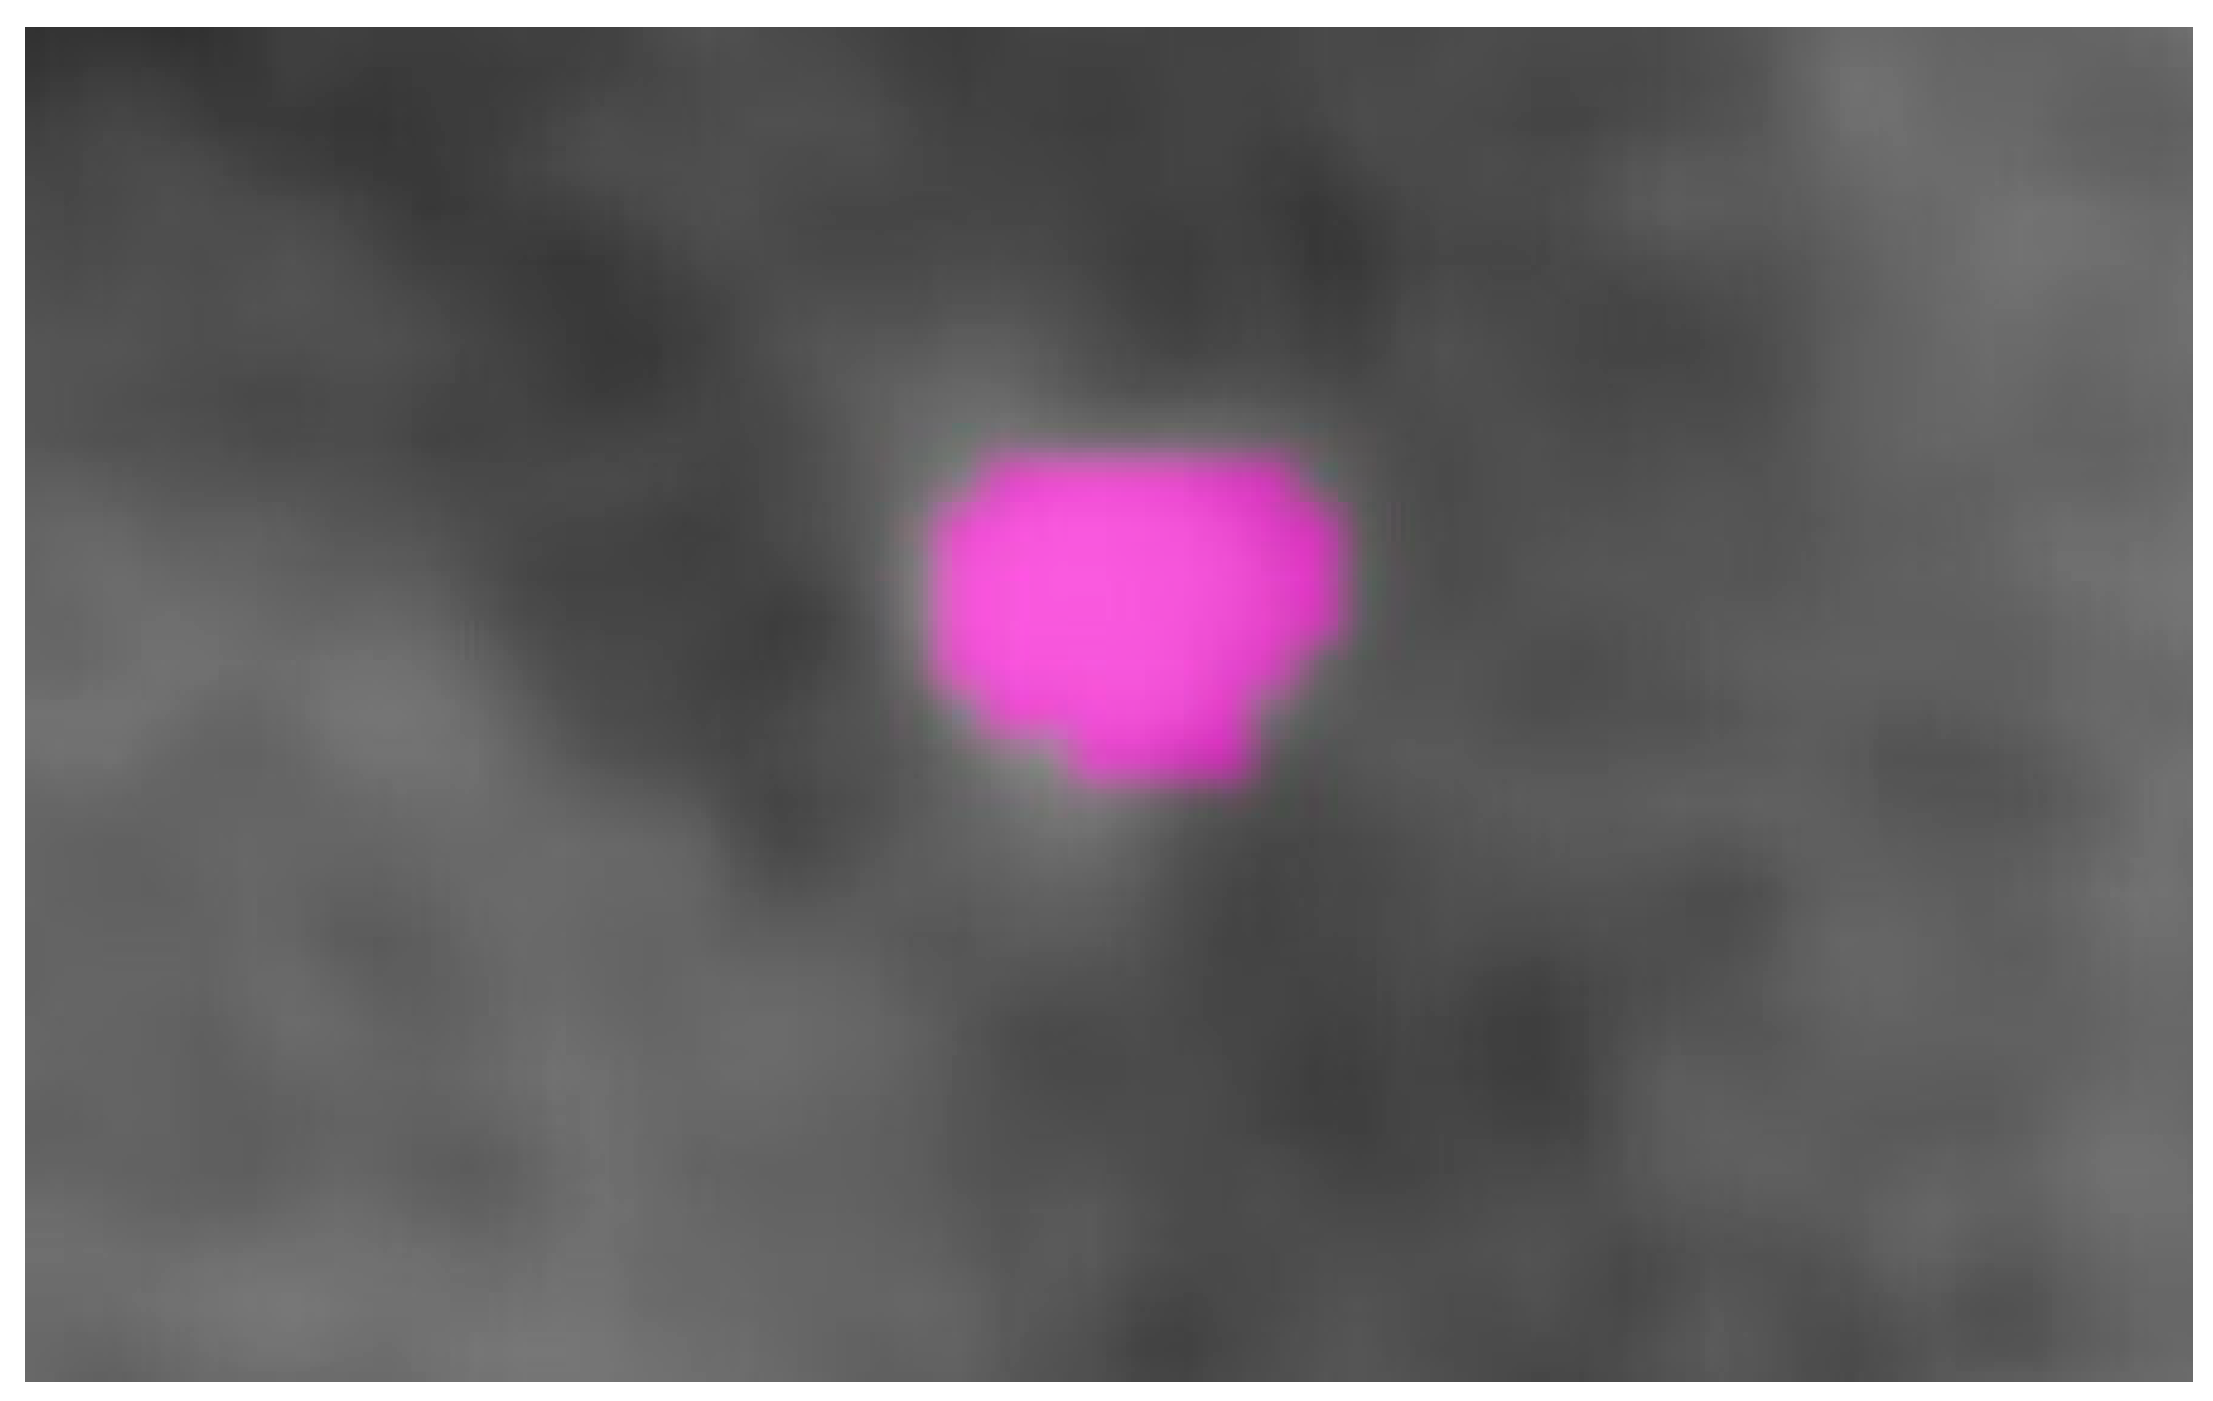

2.1. Manual Segmentation (Pencil 2D Technique) Protocol

2.2. Semiautomatic Segmentation (Circle 3D Technique) Protocol